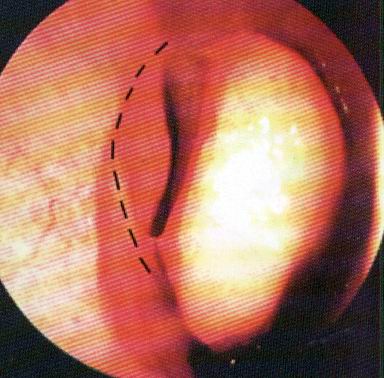

Ремарка: примечательно, что во время синуслифтинга ситуация иная - там требуется удержать барьерную мембрану на слизистой оболочке верхнечелюстной пазухи. Следовательно, рыхлая поверхность - на стороне шнайдеровой мембраны.